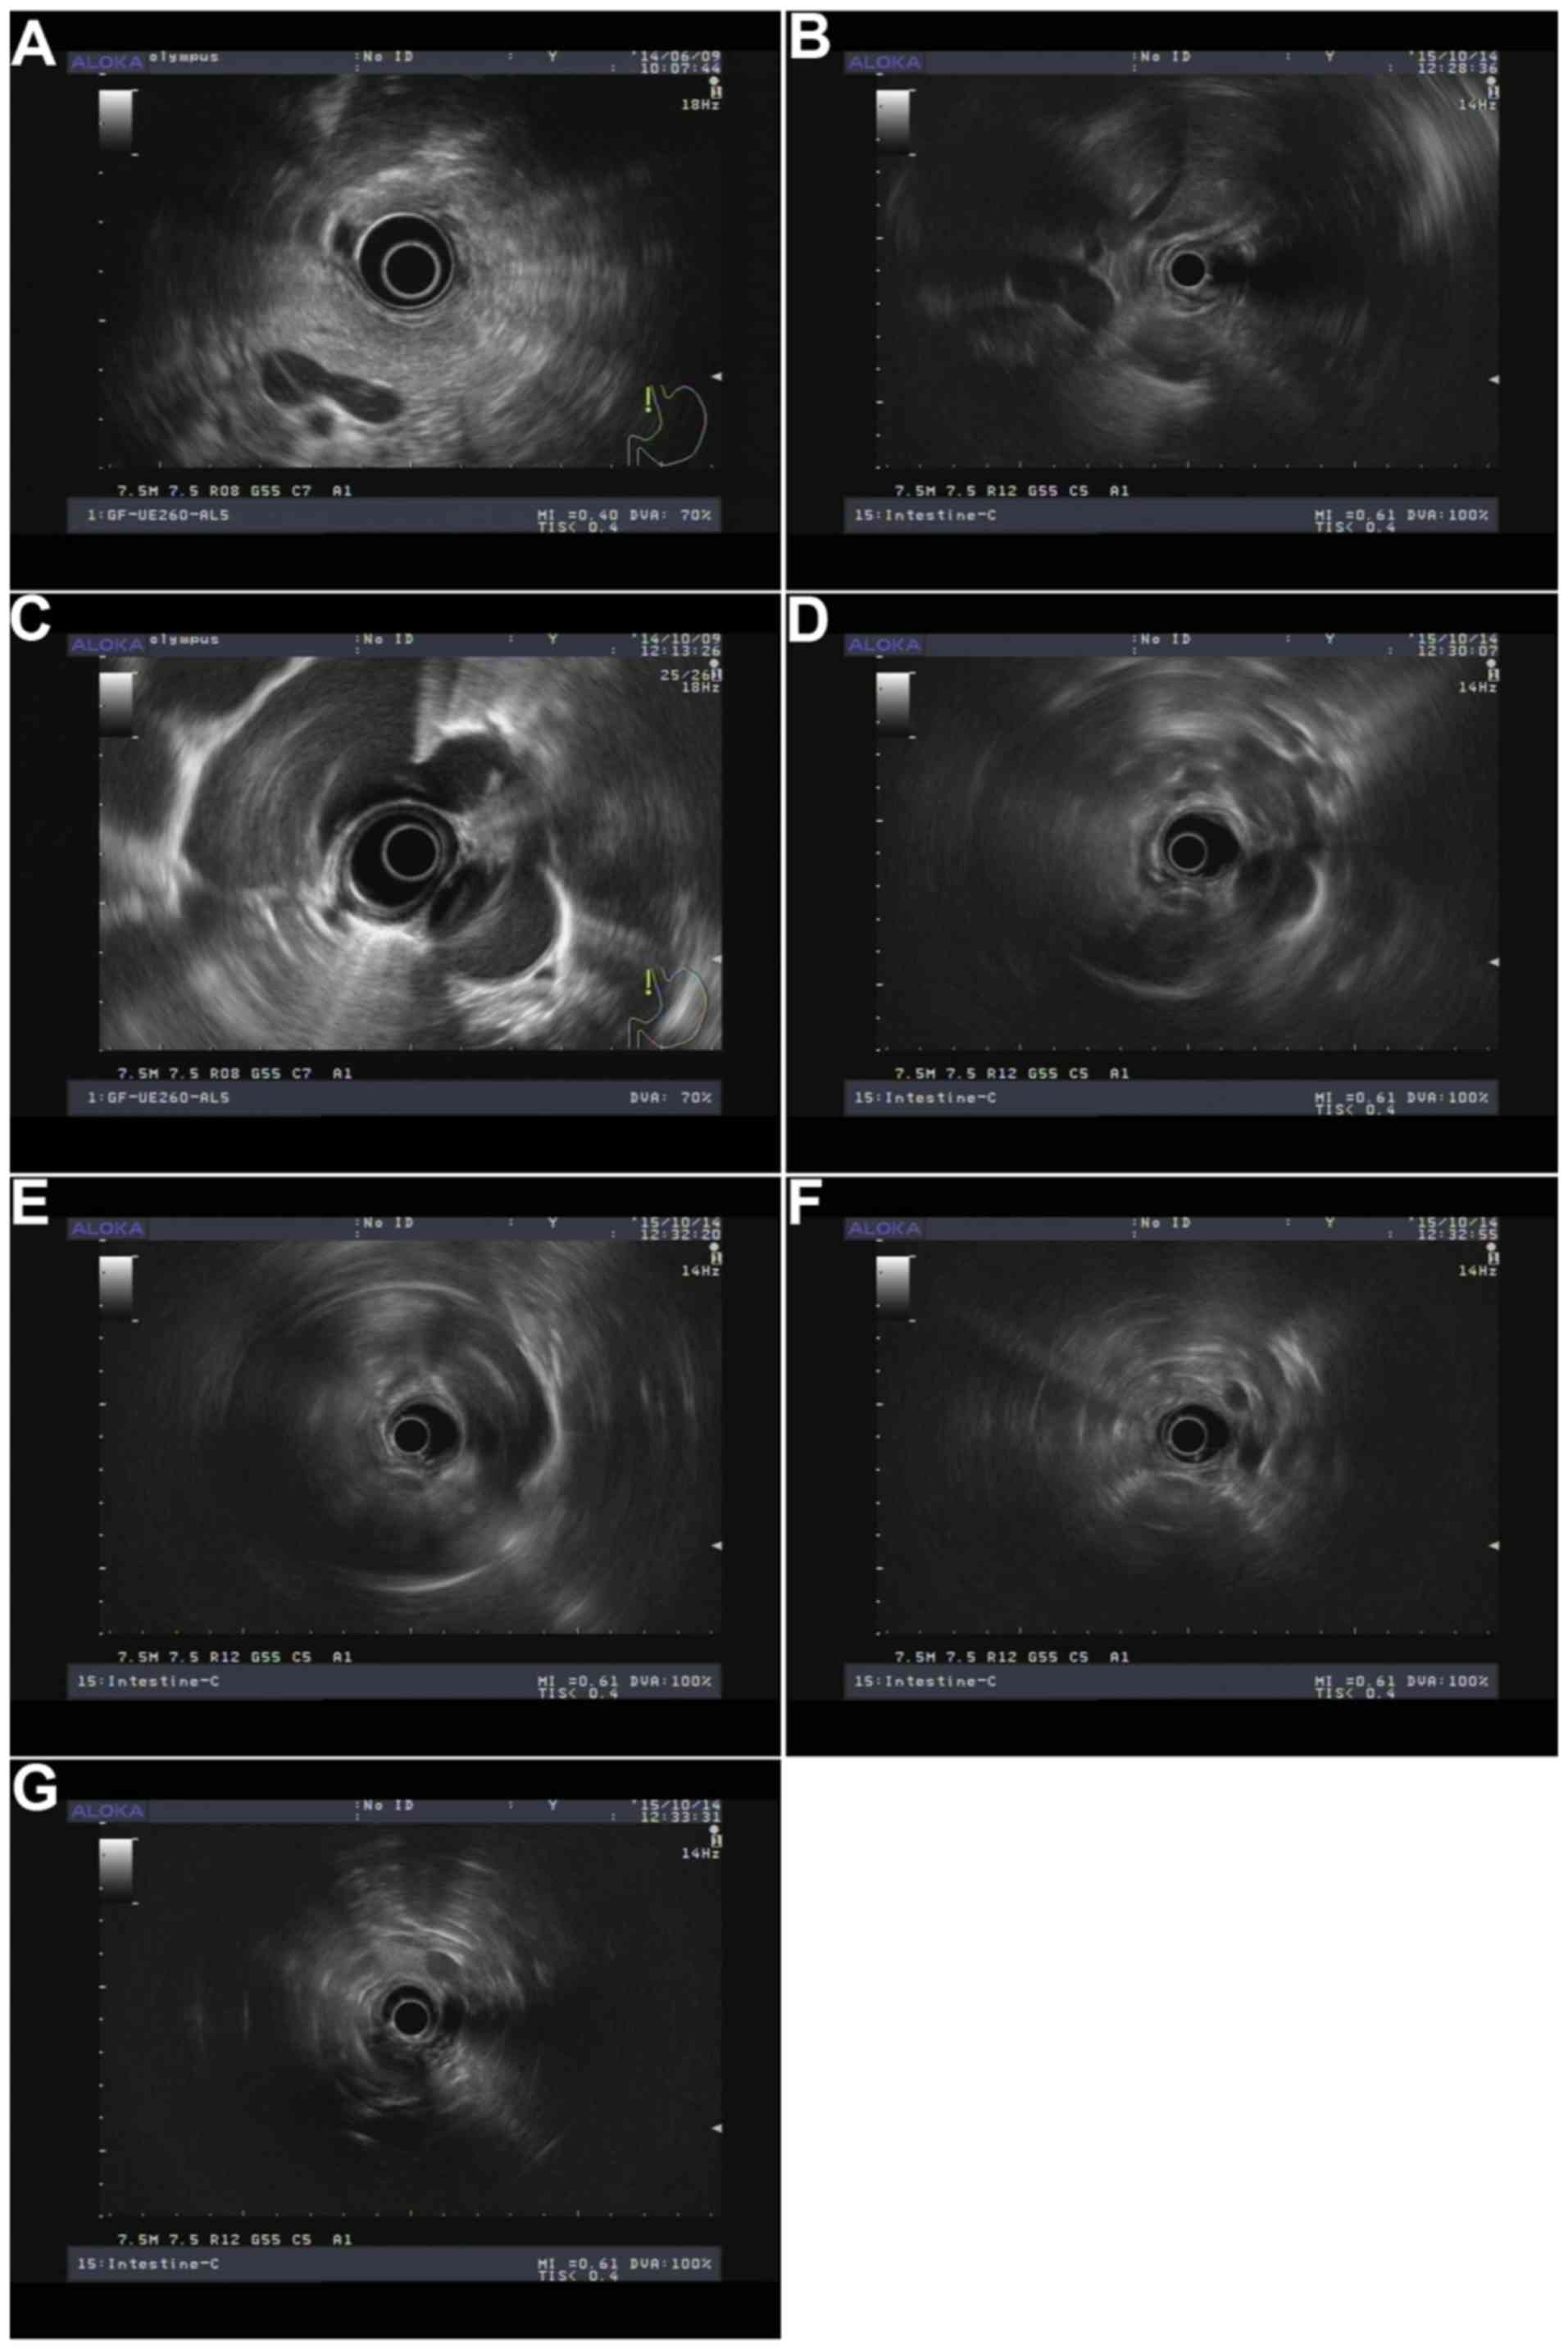

Criteria of lymph nodes

Short diameter, long diameter, short/long diameter ratio, and lymph node number were determined using AwaveAudio software (v7.2, FMJ-Software, Hagersten, Sweden). EUS clinical staging of esophageal cancer was based on the American Joint Committee on Cancer (AJCC) 2003 published guidelines (15), whilst tumor TN staging standard after surgery was based on the 7th Edition of the AJCC Manual (16). Round, low echo and smooth edge were assessed by three experienced physicians. In addition, lymph node location was determined by lymph node partition and ultrasound endoscopy of the splenic vein, the second hepatic portal, left lower pulmonary vein, carina, aortic arch, internal jugular vein, and the left thyroid area (Fig. 1): i) Para-esophageal lymph nodes near lesions; ii) left tracheal esophageal ditch, upper area of aortic arch, left esophageal, and rear-left trachea; iii) right tracheoesophageal ditch area, upper aortic arch, right esophageal, right trachea, and right rear area; iv) 4 l/5 area, carina to the aortic arch upper edge of the left front of the esophagus; v) carina, under 1 cm below the esophageal area; vi) middle of the paraesophageal area, next to the left inferior pulmonary vein and the esophageal-proximal pulmonary vein; vii) lower esophageal area, left lower pulmonary vein to the second hepatic portal; viii) pericardial lymph nodes, the second hepatic portal and the area around the inferior vena cava; ix) left gastric lymph nodes, located in the left gastric artery area; and x) retroperitoneal lymph nodes, splenic vein was marker. In addition, lymph node partition followed the standard operation of ultrasound endoscopy (Table I).

Figure 1.

Lymph node partition by endoscopic ultrasonography. (A) Splenic vein; (B) the second hepatic portal; (C) left lower pulmonary vein; (D) carina; (E) aortic arch; (F) internal jugular vein; (G) left thyroid area.